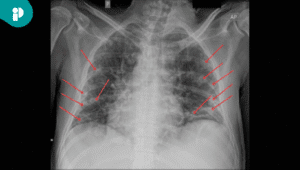

Los análisis de laboratorio mostraron inflamación elevada y eosinofilia, mientras que la biopsia confirmó fibrosis en tejido subcutáneo y fascia profunda, con infiltrados de linfocitos y células plasmáticas, hallazgos compatibles con fascitis eosinofílica.